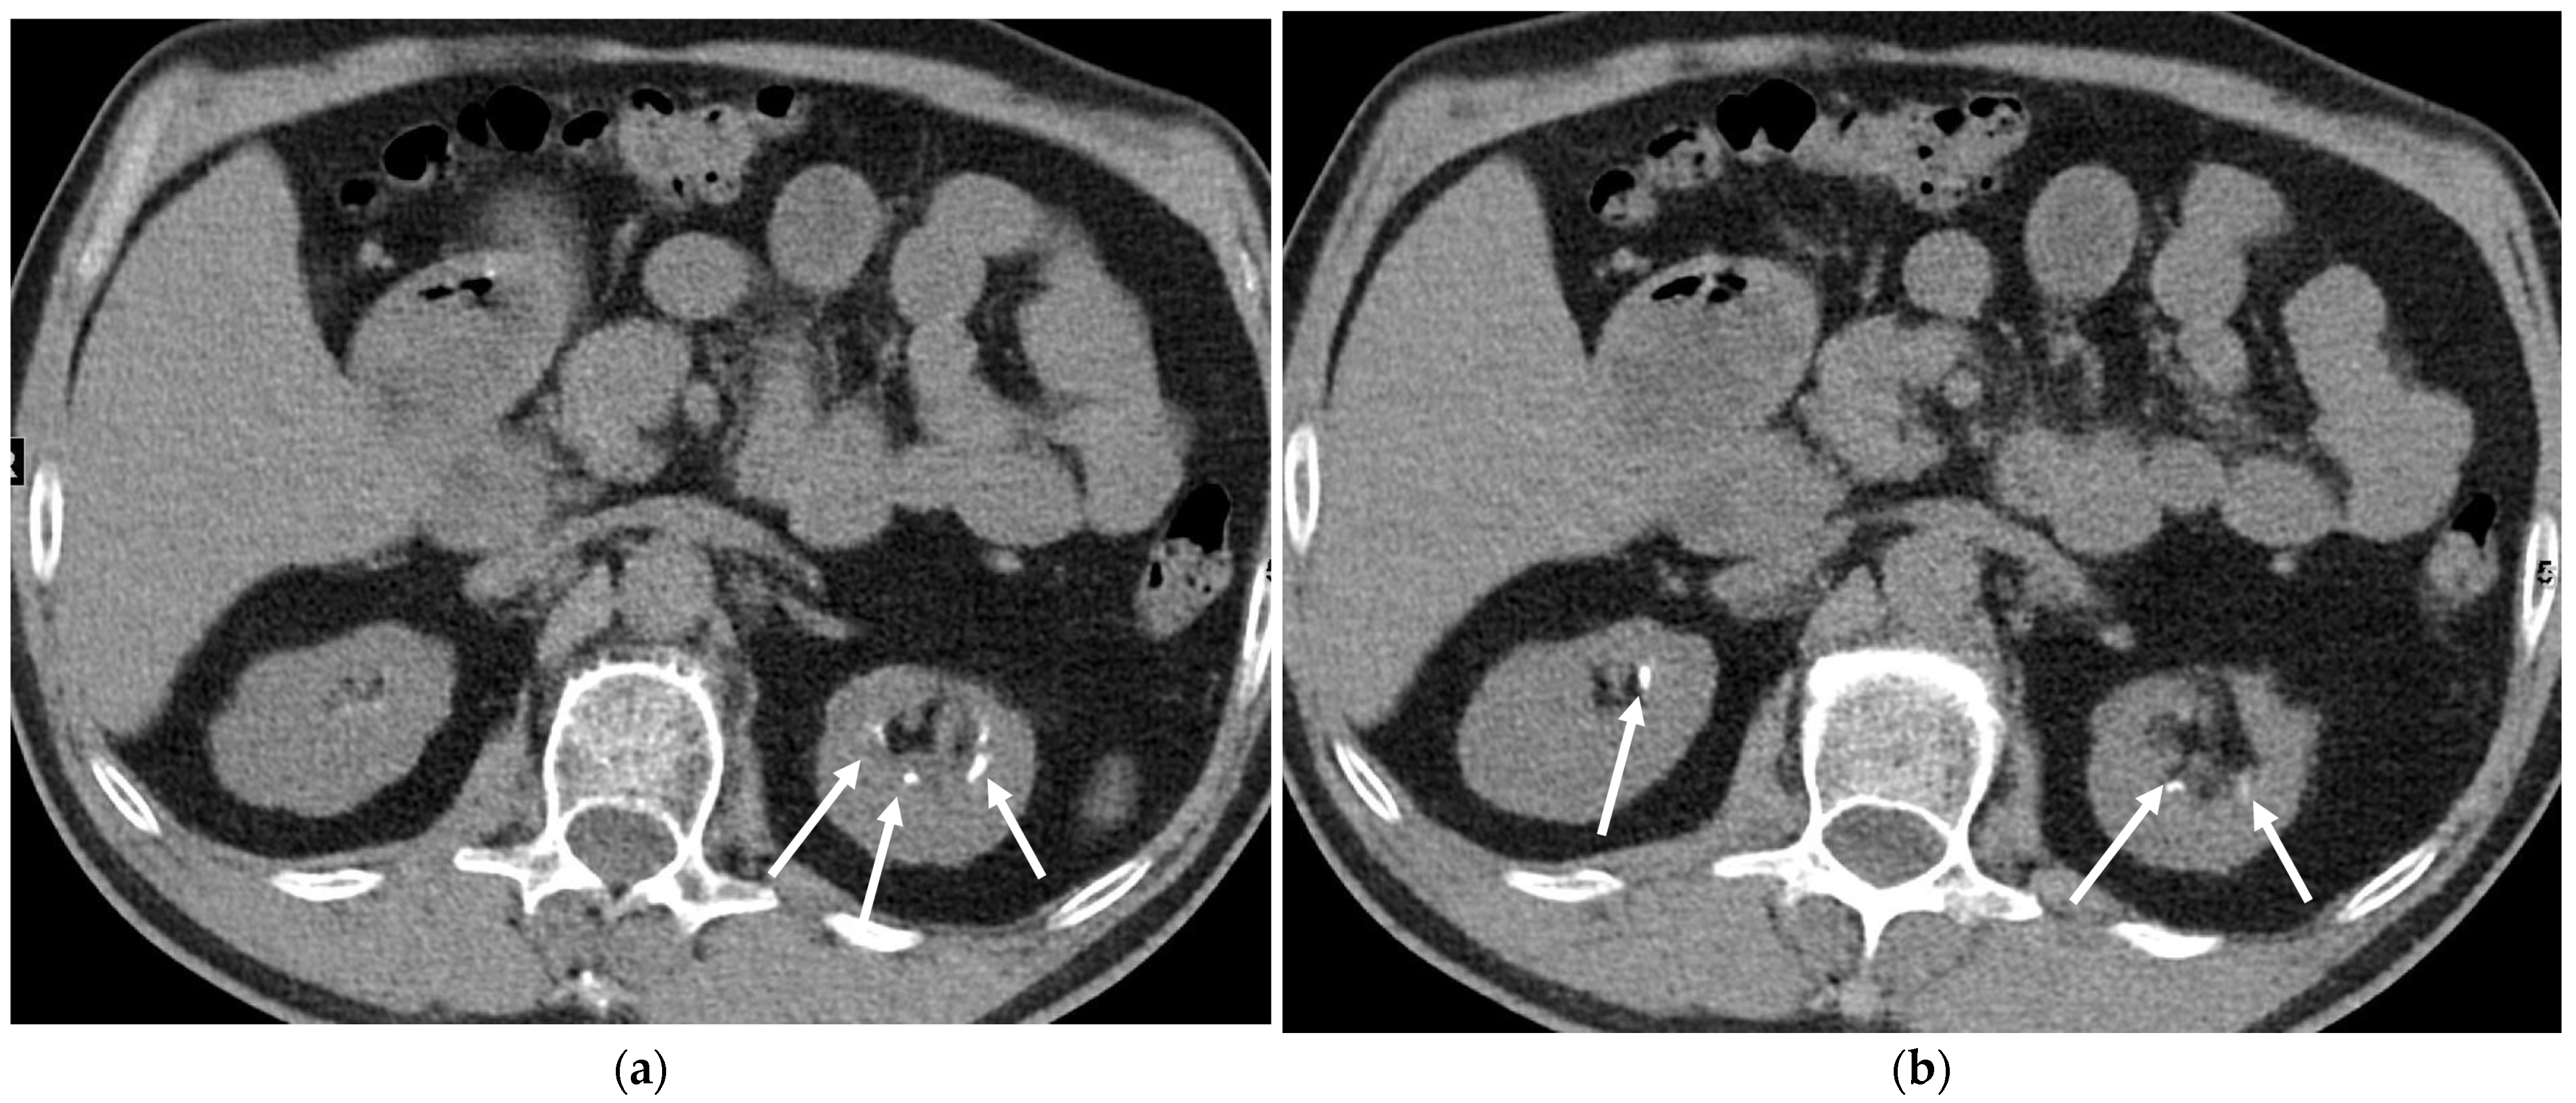

5.3.3. Kidney